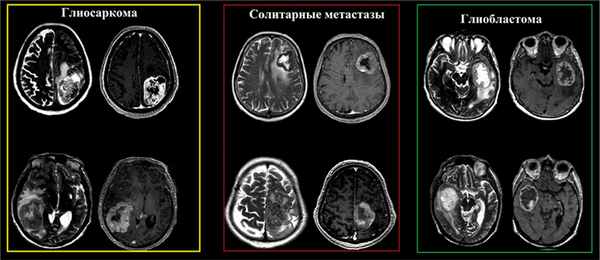

в) Дифференциальная диагностика глиосаркомы:

• Глиобластома (МГБ)

• Метастатическое поражение

• Гемангиоперицитома

• Злокачественная менингиома